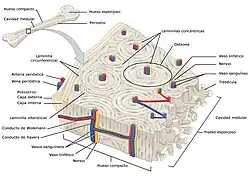

Hueso compacto (cortical)

La capa exterior dura de los huesos está compuesta de hueso cortical, que también se llama hueso compacto, ya que es mucho más denso que el hueso esponjoso, su apariencia es suave, blanca y sólida, el tejido óseo compacto o hueso cortical representa el 80 % de la masa ósea del esqueleto. Se encuentra en la diáfisis o porción central de los huesos largos, en la región exterior e interior de los huesos planos y en distintas zonas del resto de los huesos. Está constituido por capas concéntricas de laminillas óseas que forman estructuras cilíndricas llamadas osteonas,.

Facilita las funciones principales de los huesos: dar apoyo a todo el cuerpo, proteger los órganos, proporcionar palancas para el movimiento y almacenar y liberar elementos químicos, principalmente calcio. Consiste en múltiples columnas microscópicas, cada una de las cuales se llama osteón o sistema de Havers.

En el centro de los osteonas se encuentran los conductos de Havers por donde transitan los vasos sanguíneos. Los conductos de Volkmann transversales sirven para conectar varios conductos de Havers entre sí. La estructura resultante podría considerarse como un conjunto de columnas unidas por lo que presenta gran resistencia a las fuerzas de compresión.[7]

En las laminillas se ubican lagunas embutidas en el matriz mineralizada que contienen osteocitos (célula principal del tejido óseo), desde cada laguna irradian pequeños canalículos ramificados que las comunican entre sí y hacen posible la nutrición de las células.[7]

Hueso esponjoso o trabecular

El hueso esponjoso o trabecular no contiene osteonas, sino que las láminas intersticiales se disponen de forma irregular formando unas placas llamadas trabéculas. Estas placas forman una estructura esponjosa en la que se intercalan huecos llenos de médula ósea roja.

Dentro de las trabéculas se encuentran los osteocitos. Los vasos sanguíneos penetran directamente en el hueso esponjoso y permiten el intercambio de nutrientes y oxígeno entre la sangre y los osteocitos.